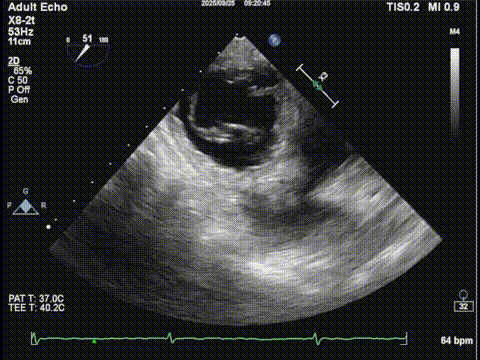

二尖瓣3D

二尖瓣3Dcolor

三尖瓣

三尖瓣反流以膈叶脱垂为主,反流主要集中在前叶和膈叶间,从中心区向边缘区的蔓延。后叶又有分了两个叶,分型上属于IIIb型的三尖瓣反流。